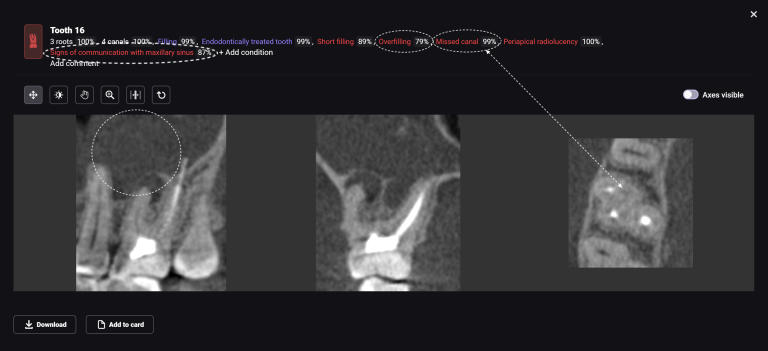

Solution: Diagnocat’s reports, based on CBCT and intraoral scans (STL files), help the clinician to quickly and accurately make decisions about treatment tactics and final tooth position, and to plan comprehensive treatment according to the individual needs of the patient